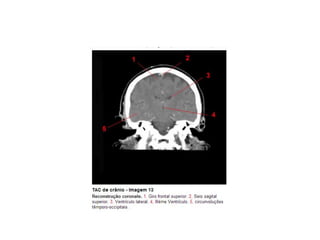

Anatomia E Protocolo Tomografia Computadorizada de Crânio PPT